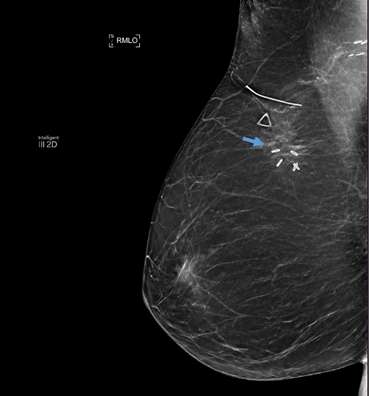

Case: Fat Necrosis of Breast Figure 2

Figure 2: 69 year old female patient with history of right breast cancer status post lumpectomy, with a newly palpable mass in the right breast. Right MLO view, and companion image to Figure 1. The patient has a radiolucent oval mass (blue arrow) at the site of prior surgical incision with spiculated surrounding scarring/post-surgical change. In the setting of recent surgery, this appearance is consistent with fat necrosis. No further evaluation was recommended.